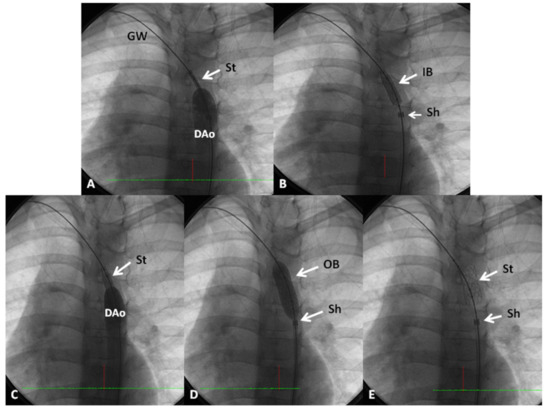

4. Coarctation of the Aorta

4.3. Type of Intervention